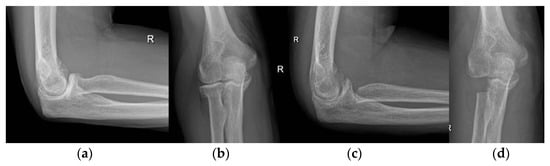

- Martinez-Catalan, N.; Sanchez-Sotelo, J. Primary Elbow Osteoarthritis: Evaluation and Management. J. Clin. Orthop. Trauma 2021, 19, 67–74. [Google Scholar] [CrossRef]

- Kwak, J.-M.; Jeon, I.-H. Surgical Management for Primary Osteoarthritis of the Elbow. J. Orthop. Surg. Hong Kong 2021, 29, 2309499020988174. [Google Scholar] [CrossRef]